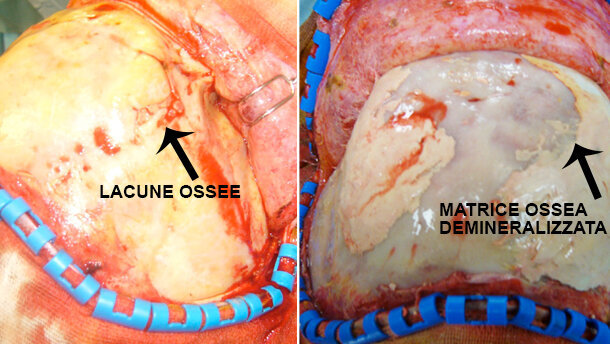

- le lacune ossee sono state trattate mediante cranioplastica; in un caso si procedeva inoltre a rimodellamento fronto-orbitario. Le cranioplastiche sono state effettuate con diversi materiali: osso autologo, metilmetacrilato, matrice ossea demineralizzata (Fig. 1) e cemento;

embedImagecenter("Imagecenter_2_1124",1124,"small");